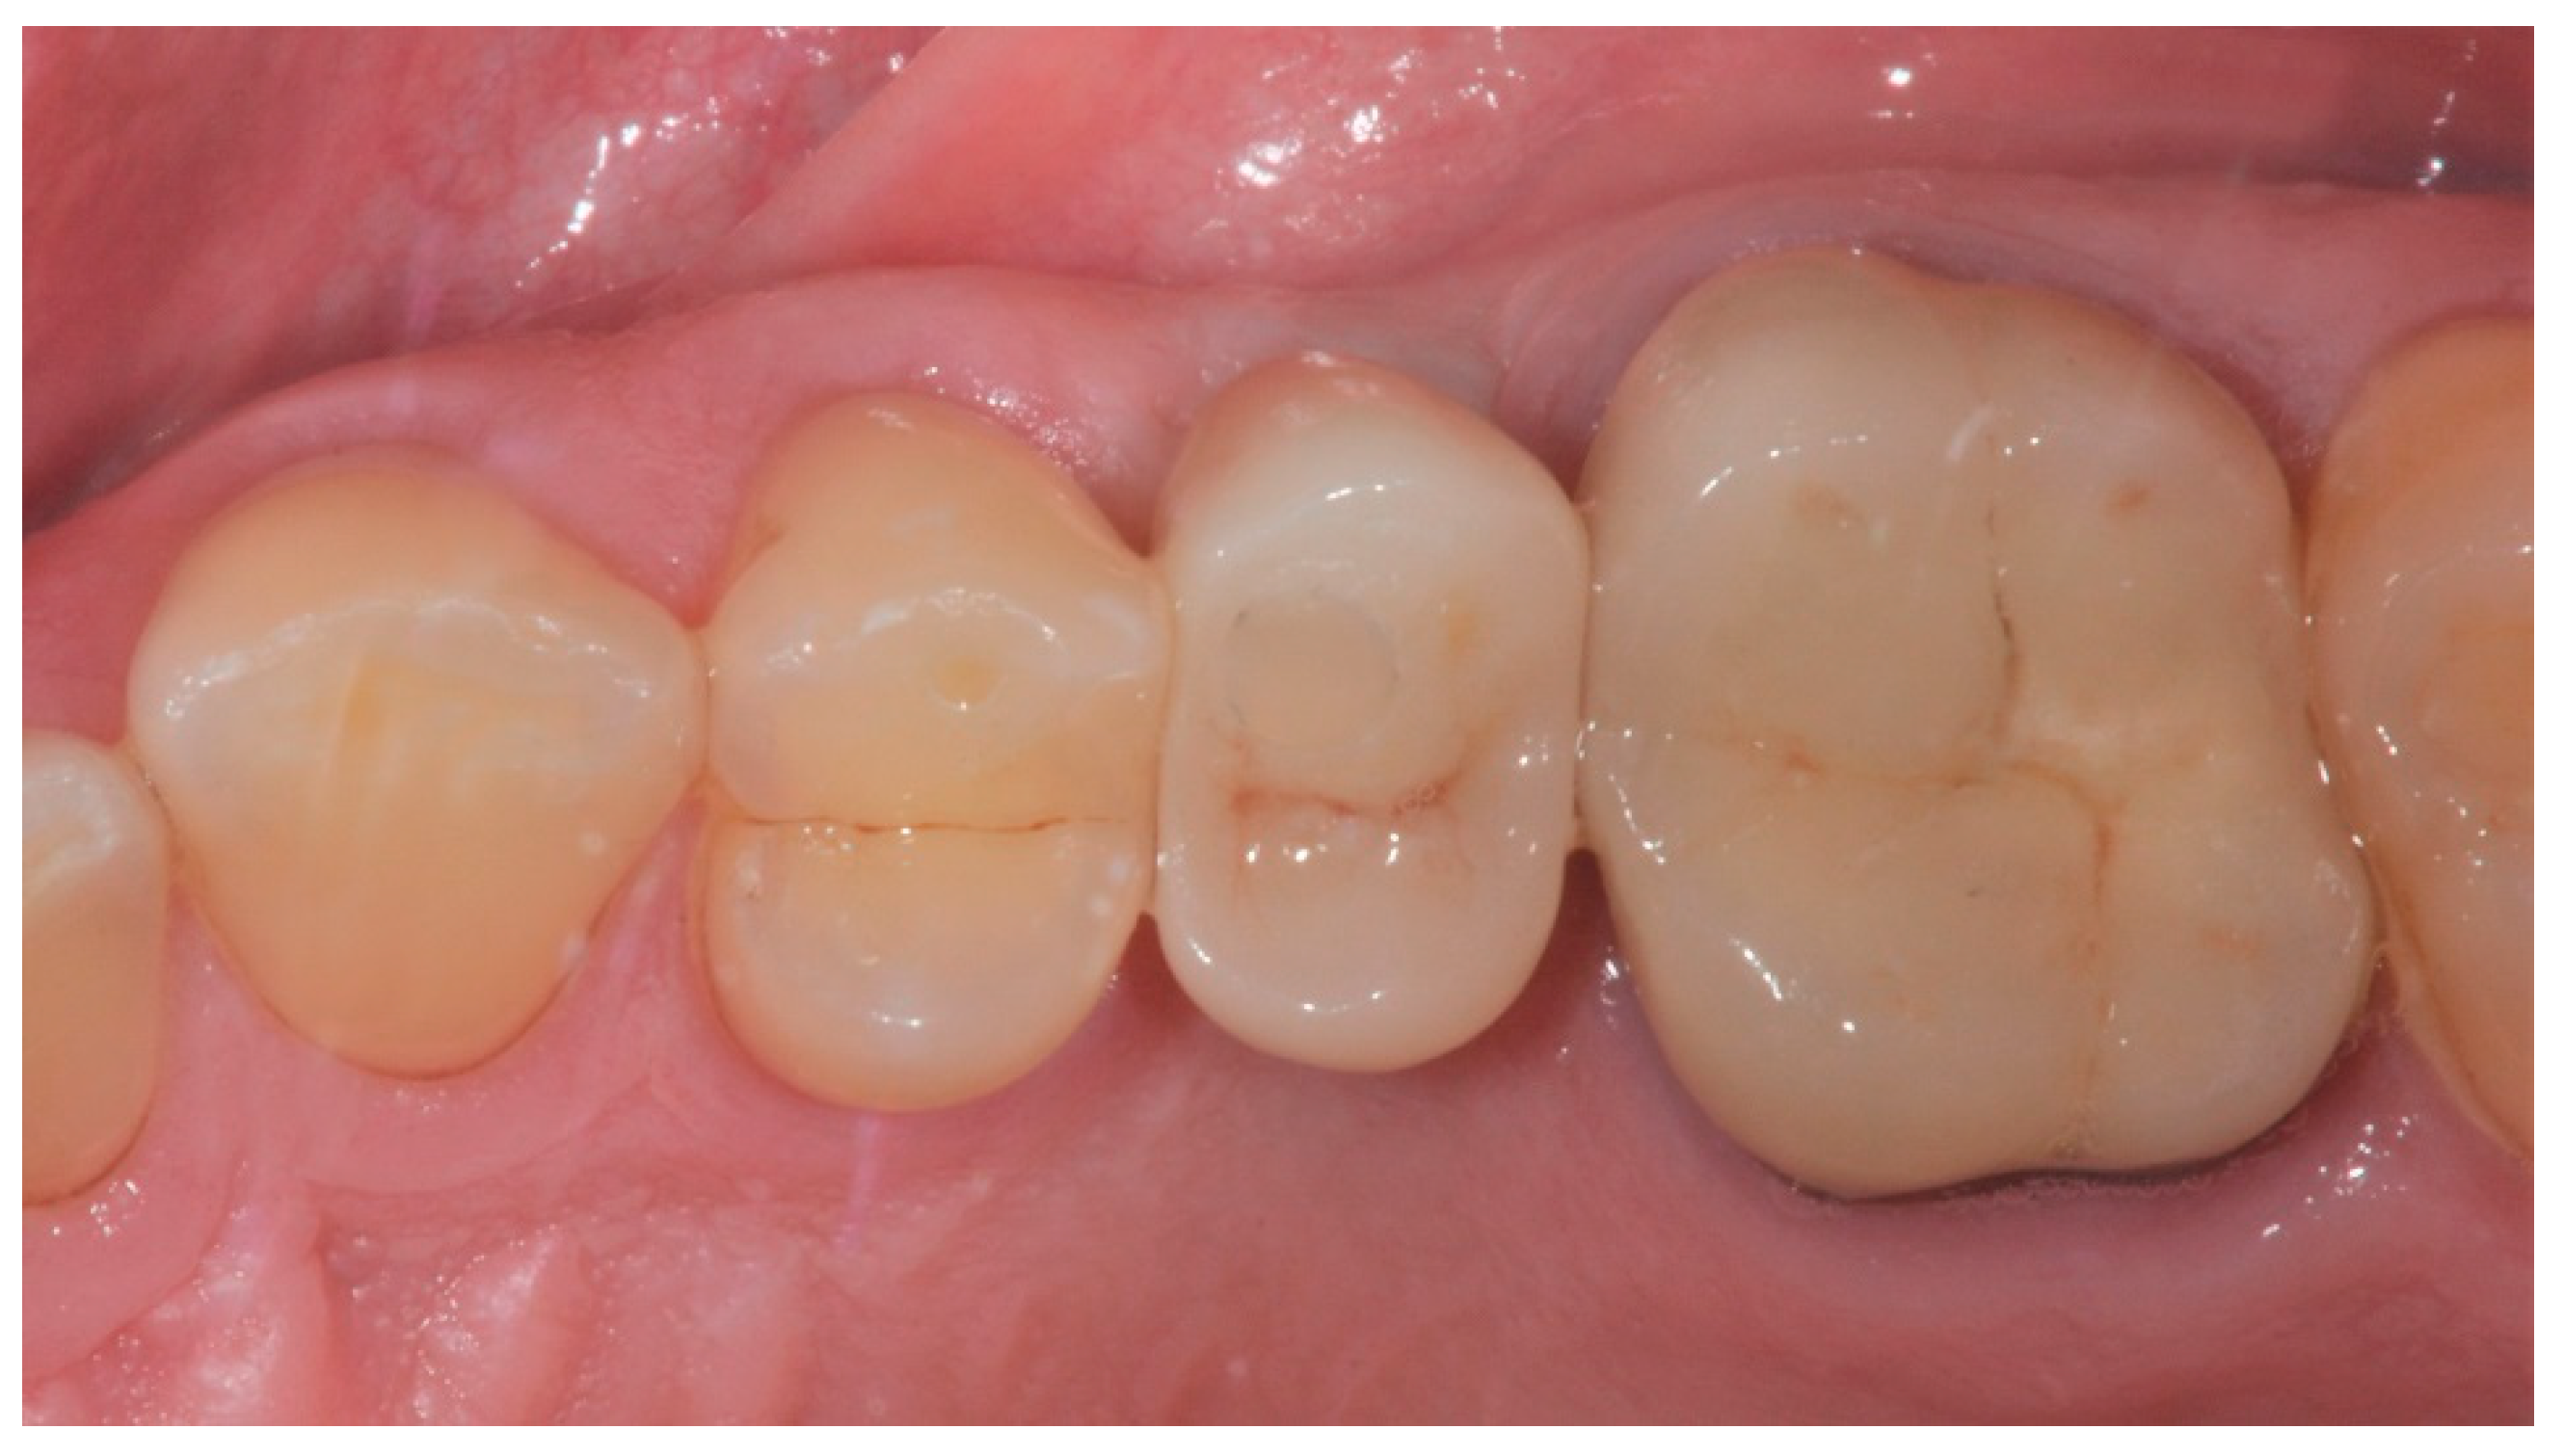

2.3. Prosthetic Protocol